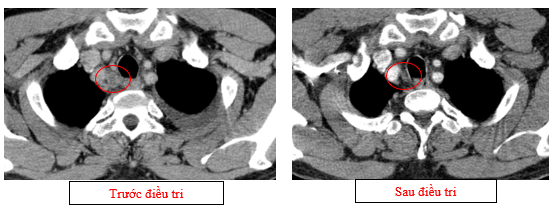

- Chụp cắt lớp vi tính lồng ngực (08/2025): Khối rốn phổi trái ôm quanh nhánh phế quản thùy dưới trái kích thước 28x26mm, dày tổn chức kẽ vách liên tiểu thùy và nhiều nốt đặc lan tỏa khắp nhu mô, đường kính <7mm. Màng phổi trái có vài nốt đặc ngấm thuốc nốt lớn nhất kích thước 17x15mm Khoang màng phổi trái có dịch dày 54mm. Nhiều hạch to trung thất, rốn phổi hai bên và hố thượng đòn có hoại tử trung tâm, hạch lớn nhất kích thước trục ngắn 22mm.

- Chụp cắt lớp vi tính lồng ngực (11/2025): Màng phổi vùng rốn phổi trái dày, dày tổ chức kẽ vùng ngoại vi đáy phổi hai bên. Màng phổi trái có vài nốt đặc ngấm thuốc nốt lớn nhất kích thước 17x15mm. Khoang màng phổi hai bên không có dịch – khí (Tổn thương giảm đáng kể so với phim chụp 08/2025). Trung thất, rốn phổi hai bên, hố thượng đòn trái có vài hạch, hạch lớn nhất kích thước 12x6mm. Vài nốt đặc xương rải rác thân đốt sống, các cung xương sườn hai bên.

Hình 10: Không còn thấy tổn thương hạch trung thất nhóm 2 sau điều trị